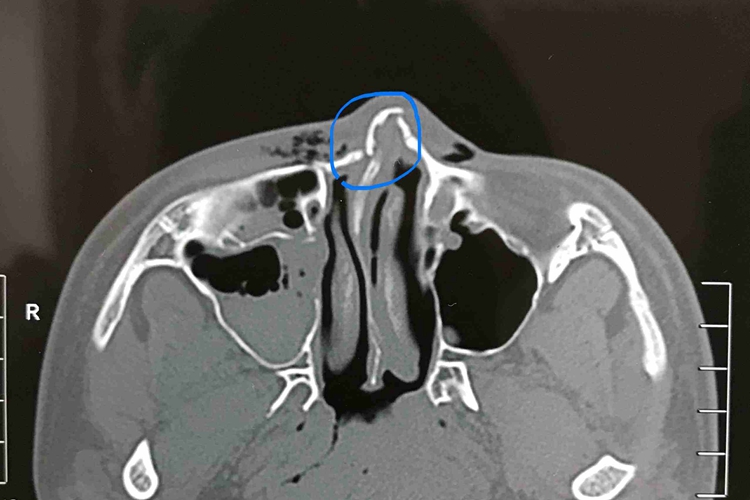

幼儿鼻梁骨折时,可出现鼻梁歪斜、鼻背塌陷和畸形。鼻中隔明显偏曲移位或有血肿形成,可造成一侧或双侧鼻塞。擤鼻时气体经撕裂的鼻腔黏膜进入眼及颊部皮下组织,可出现皮下气肿等。鼻局部触痛,触之可感鼻骨塌陷和骨擦音,皮下气肿可触之有捻发音。鼻畸形常被肿胀所掩盖。若有中隔血肿,可见中隔黏膜向一侧或两侧膨隆。

幼儿鼻梁骨折应在外伤后数小时内尽早前往医院处理,一般不宜超过2周,以免发生畸形愈合。无错位性骨折无须复位;错位性骨折可在鼻腔表面麻醉行鼻内或鼻外复位,开放性鼻骨骨折应争取一期完成清创缝合与鼻骨骨折的复位,鼻中隔损伤出现偏曲、脱位等情况时应做开放复位。鼻中隔血肿脓肿应尽早手术清除,避免发生软骨坏死和继发感染;对鼻骨粉碎性骨折应视具体情况做缝合固定、鼻腔内填塞等;鼻腔填塞物一般48-72小时取出。